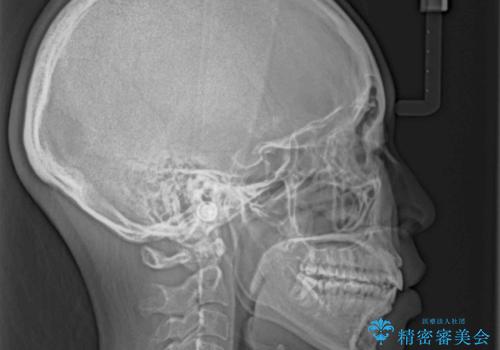

気がつくと唇が開く 口元を下げる抜歯矯正

- 口が閉じにくさを気にして来院された患者様です。

上下の前歯が前方に突出していたため、上下左右の第一小臼歯4本を抜歯し、ワイヤー装置にて抜歯矯正を行うこととしました。

上下前歯部の被蓋関係を改善するの時間がかかり、3年間を要することとなりましたが、スッキリとした口元に仕上がりました。